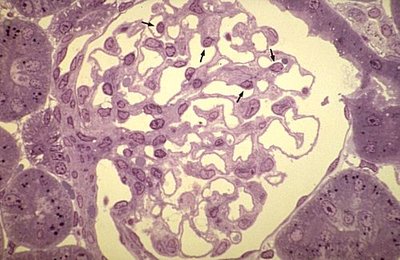

à mon avis ça existe pas...) Les exemples connus c'est la paroi des vaisseaux -> endothélium (image 1) / les cavités des reins (image 2)